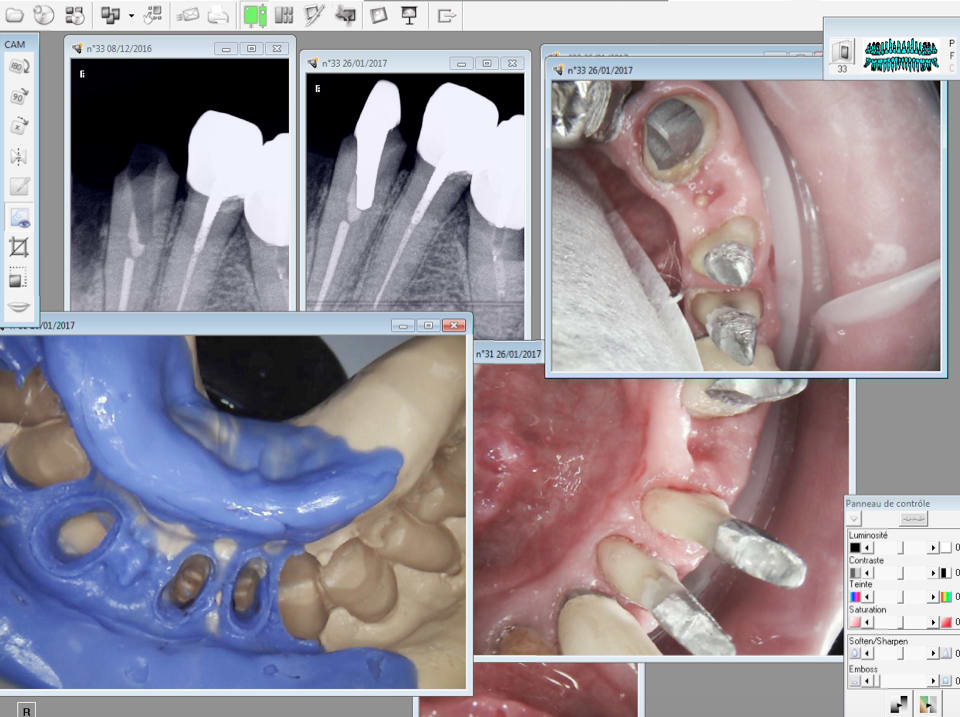

Suite et presque fin. -)

Capture d écran 2017 01 26 12.10 - Eugenol

26/01/2017 à 12h17

Chronique d'une fracture annoncée :-))

Y'a des chances que ça finisse comme ça...

Ca va mal finir c'est sur. Il est au courant. Ceci dit je doute que ca soit à cause de la canine. -)

Moi pas comprendre : la couronne sur la 2 a un an ? et la dent est extraite ? et maintenant tu fais un bridge là dessus ? Décidément chicot , nous n'avons vraiment pas les mêmes valeurs ...PB paro +++ , caries +++ , c'est de l'acharnement thérapeutique . C'est normal , tu me diras , c'est un ami ! .

ok casa, tu ferais quoi toi? sans animosité :)

Ami ou pas, direct claquos ? C'est un peu chaud quand même, non ?

Elle a eu quoi la 32 ? Fracture, ou Pb endo (j'en doute hein Chicot) ? ou endo/paro ?

Problème paro.